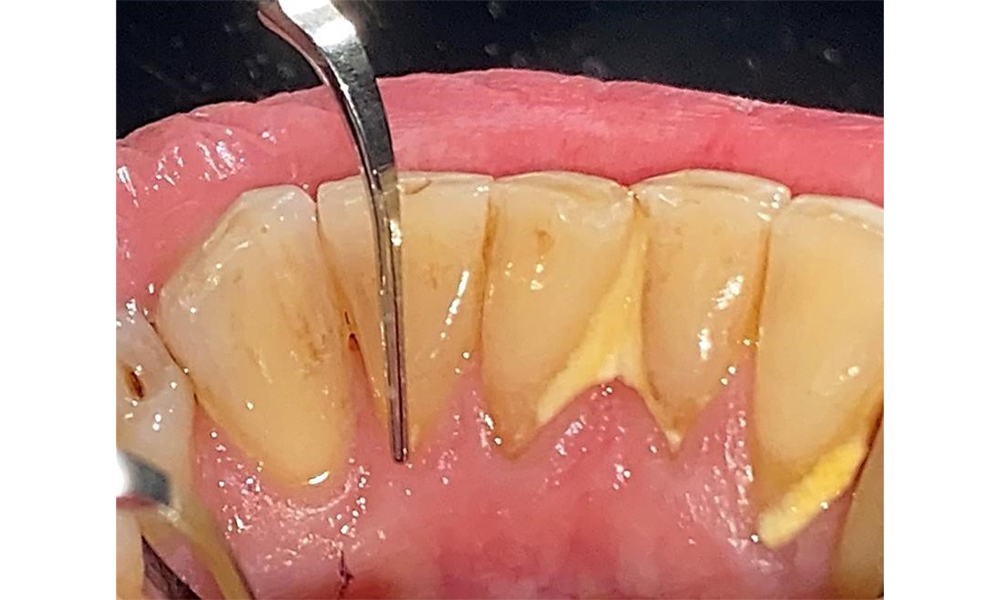

The documentation of periodontal findings, including pocket depth probing and bleeding status, is mandatory during each dental appointment due to the presence of periodontitis (Fig. 8). This will record the individual therapeutic needs and facilitate a rapid response to any progression of the pre-existing periodontitis.

Probing to document the findings in tooth 27 mesiopalatal.

Fig. 8: Probing to document the findings in tooth 27 mesiopalatal. © Dr R. Krapf